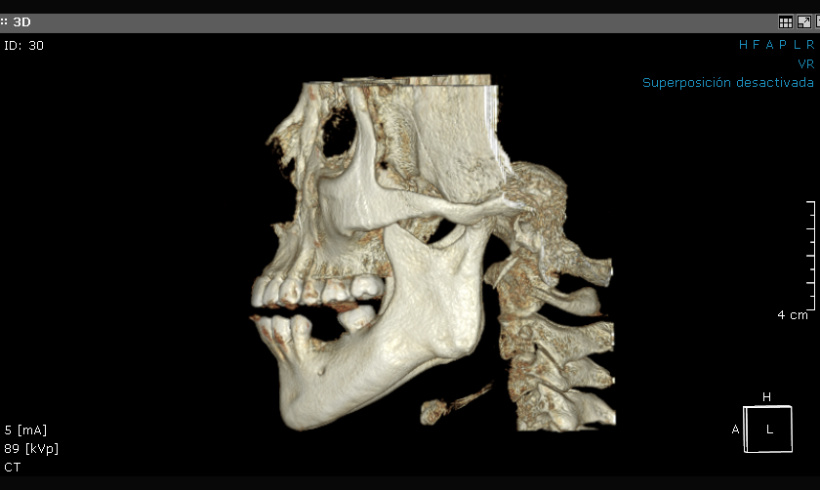

La tomografía, junto con el escaneo nos permite realizar guías quirúrgicas para la colocación de implantes, alargamiento de coronas, colocación de mini implantes de ortodoncia, tratar endodóndicamente dientes calcificados.

Tomografía para guías quirúrgicas